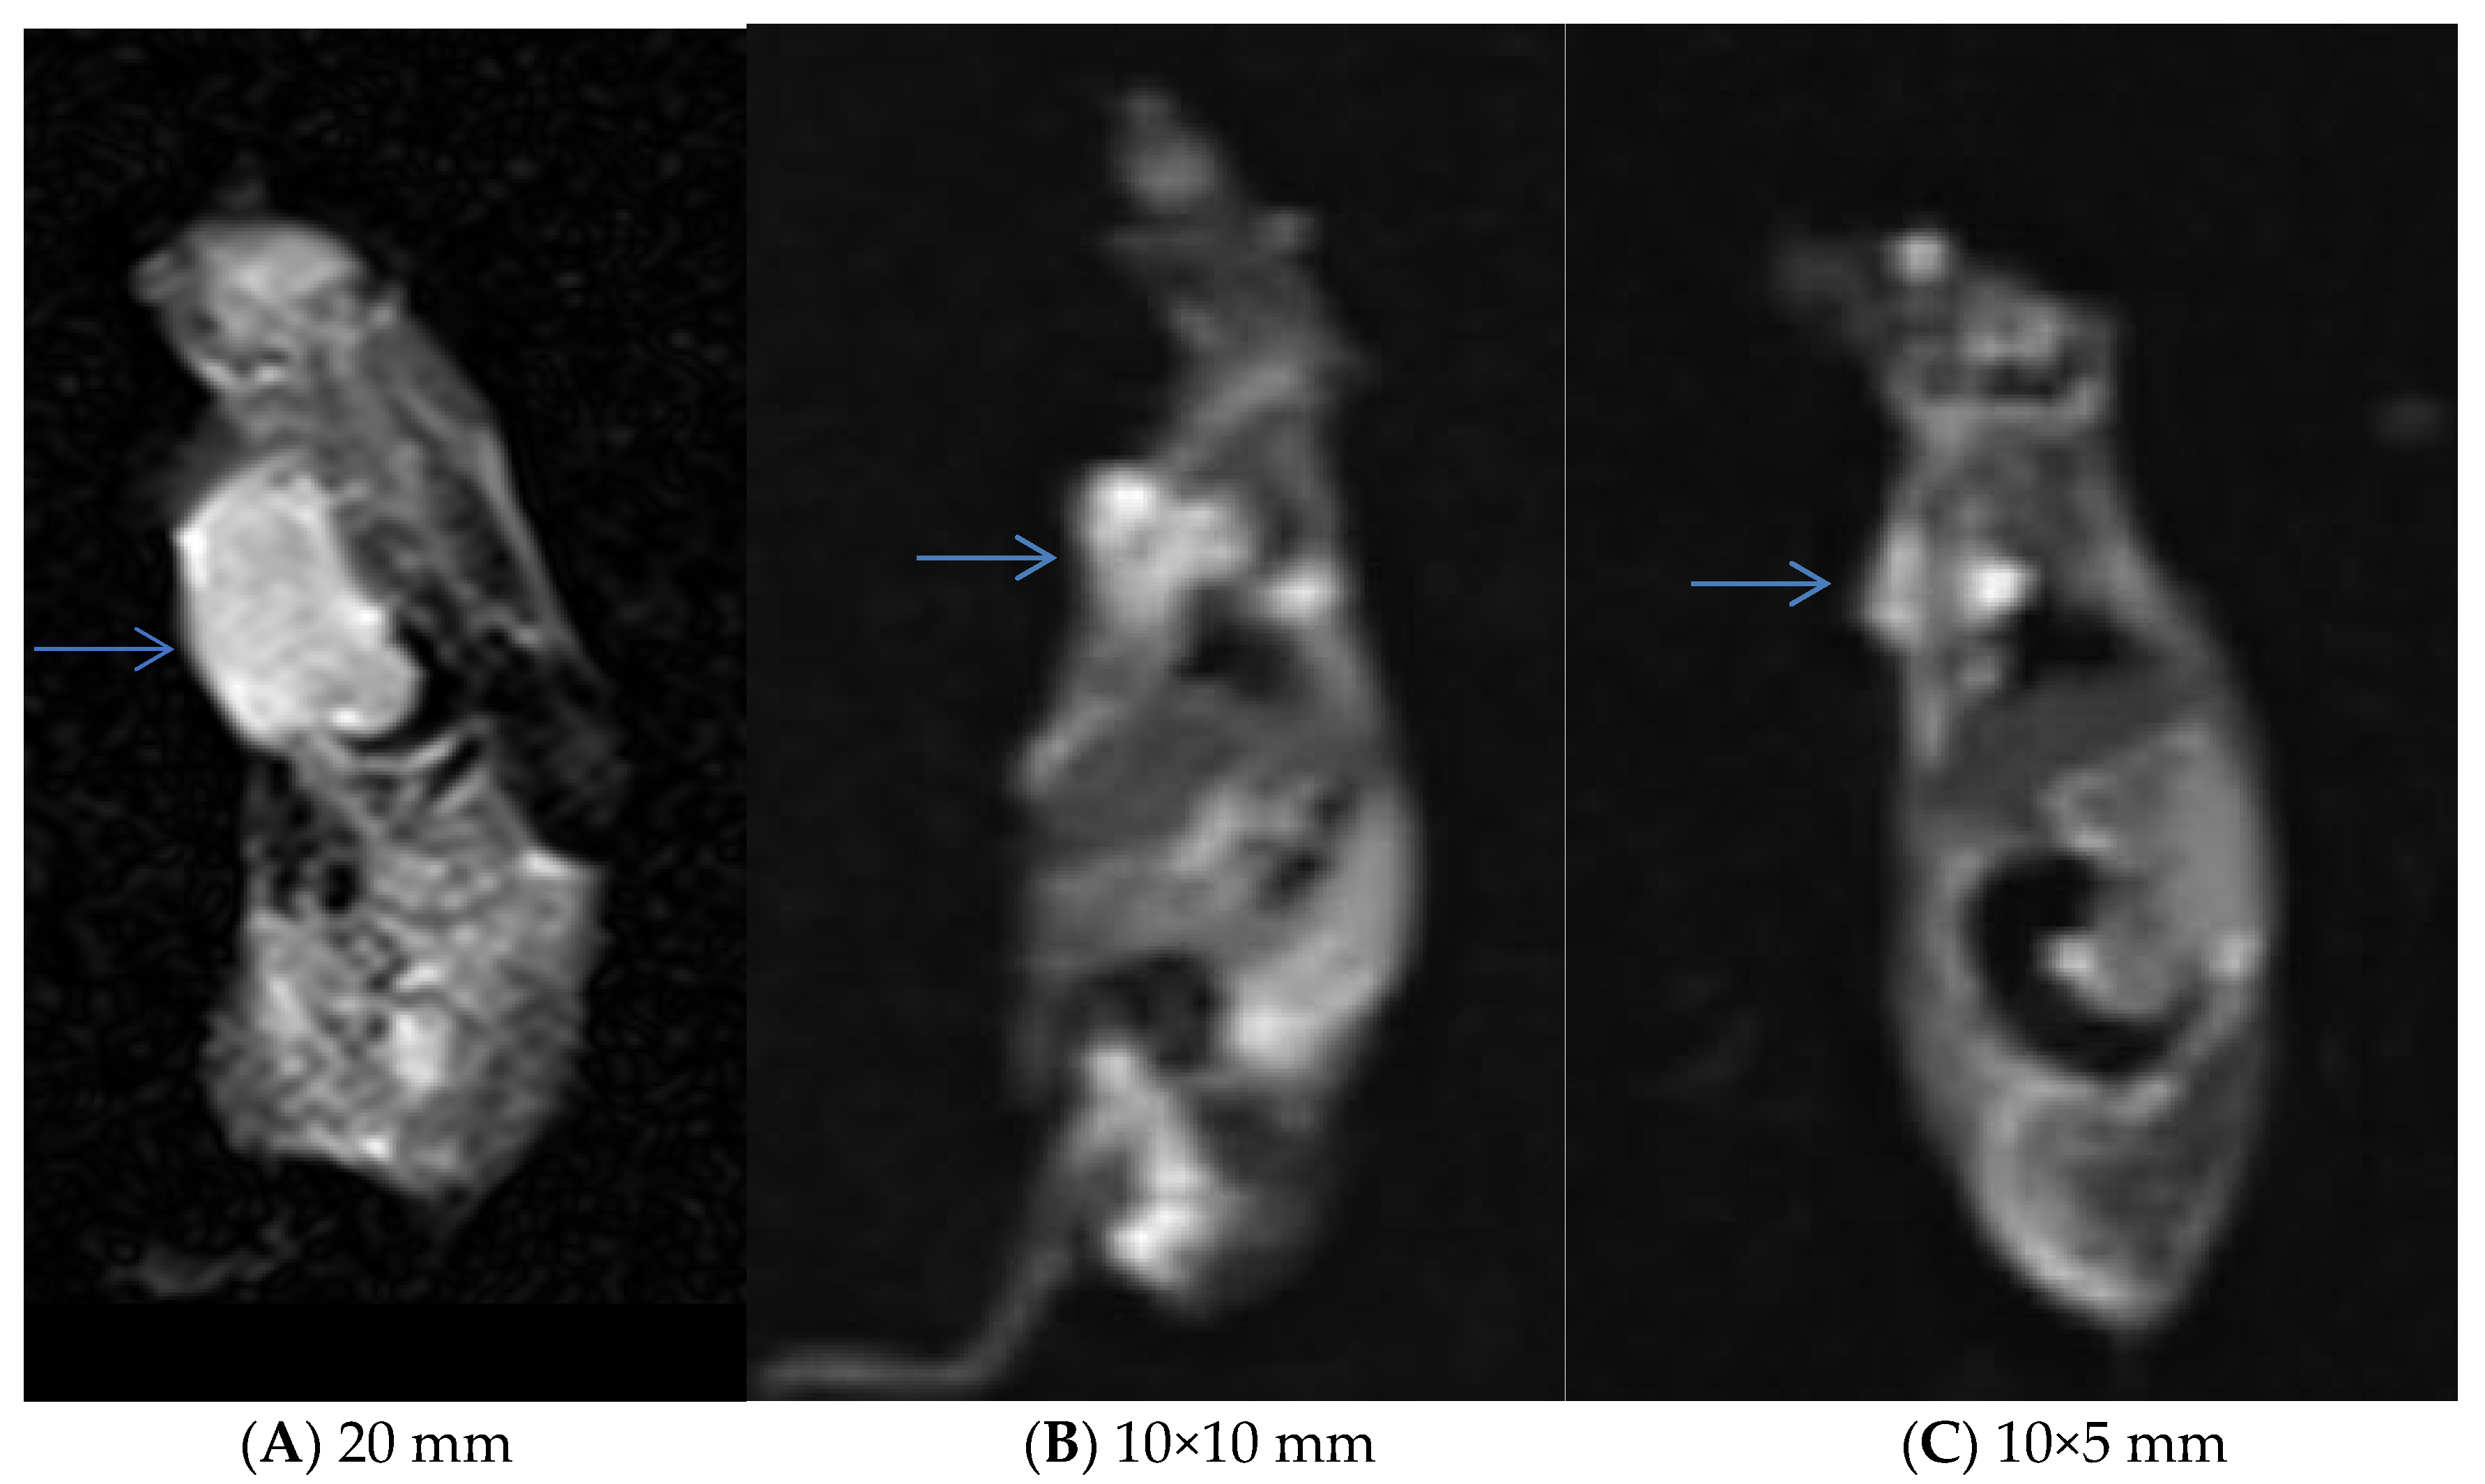

2.12. MRI Imaging

3.5. In Vivo Experiments and MRI Analysis